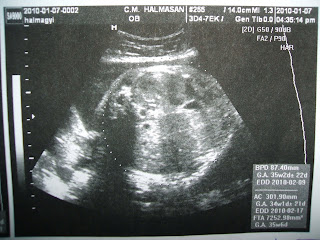

Ma újra voltunk ultrahangos vizsgálaton, illetve az első kardiotokogramos vizsgálaton (CTG), amely a magzat (vagyis a TE) szívhangjait, mozgását és a méh tónusát detektálja (monitorizálás). Anya már alig várta ezt a pillanatot! Nagyszerű érzés volt látni, hogy a mozgásaid összhangban vannak a szívhanggal, illetve a méh tónusával: minden jól működik :) Bár a dokinéni méhösszehúzódásokat észlelt, viszont annyira gyengék lehettek, hogy Anya nem is érezte őket (valószínűleg csak belső összehúzódások voltak), de mostantól már bármikortól erösődhetnek a fájdalmak.

Mostani körülbelüli súlyod: 2570 gramm (690 grammot nőttél az utolsó vizsgálattól).Anya súlya: 68 kg (eddig 9 kg súlyfelesleg), vérnyomása: 110/70, a méhlepény mostantól már kezd öregedni, de még jó állapotban van, illetve elegendő a magzatvíz mennyisége is. A héten hüvelyi vizsgálatot is végzett a dokinéni: mindent rendben talált, nincs semmilyen fertőzés.